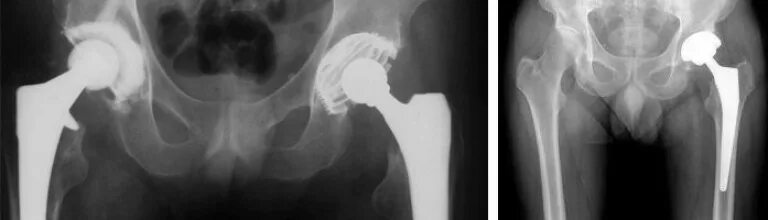

Эндопротез тазобедренного сустава мкб 10